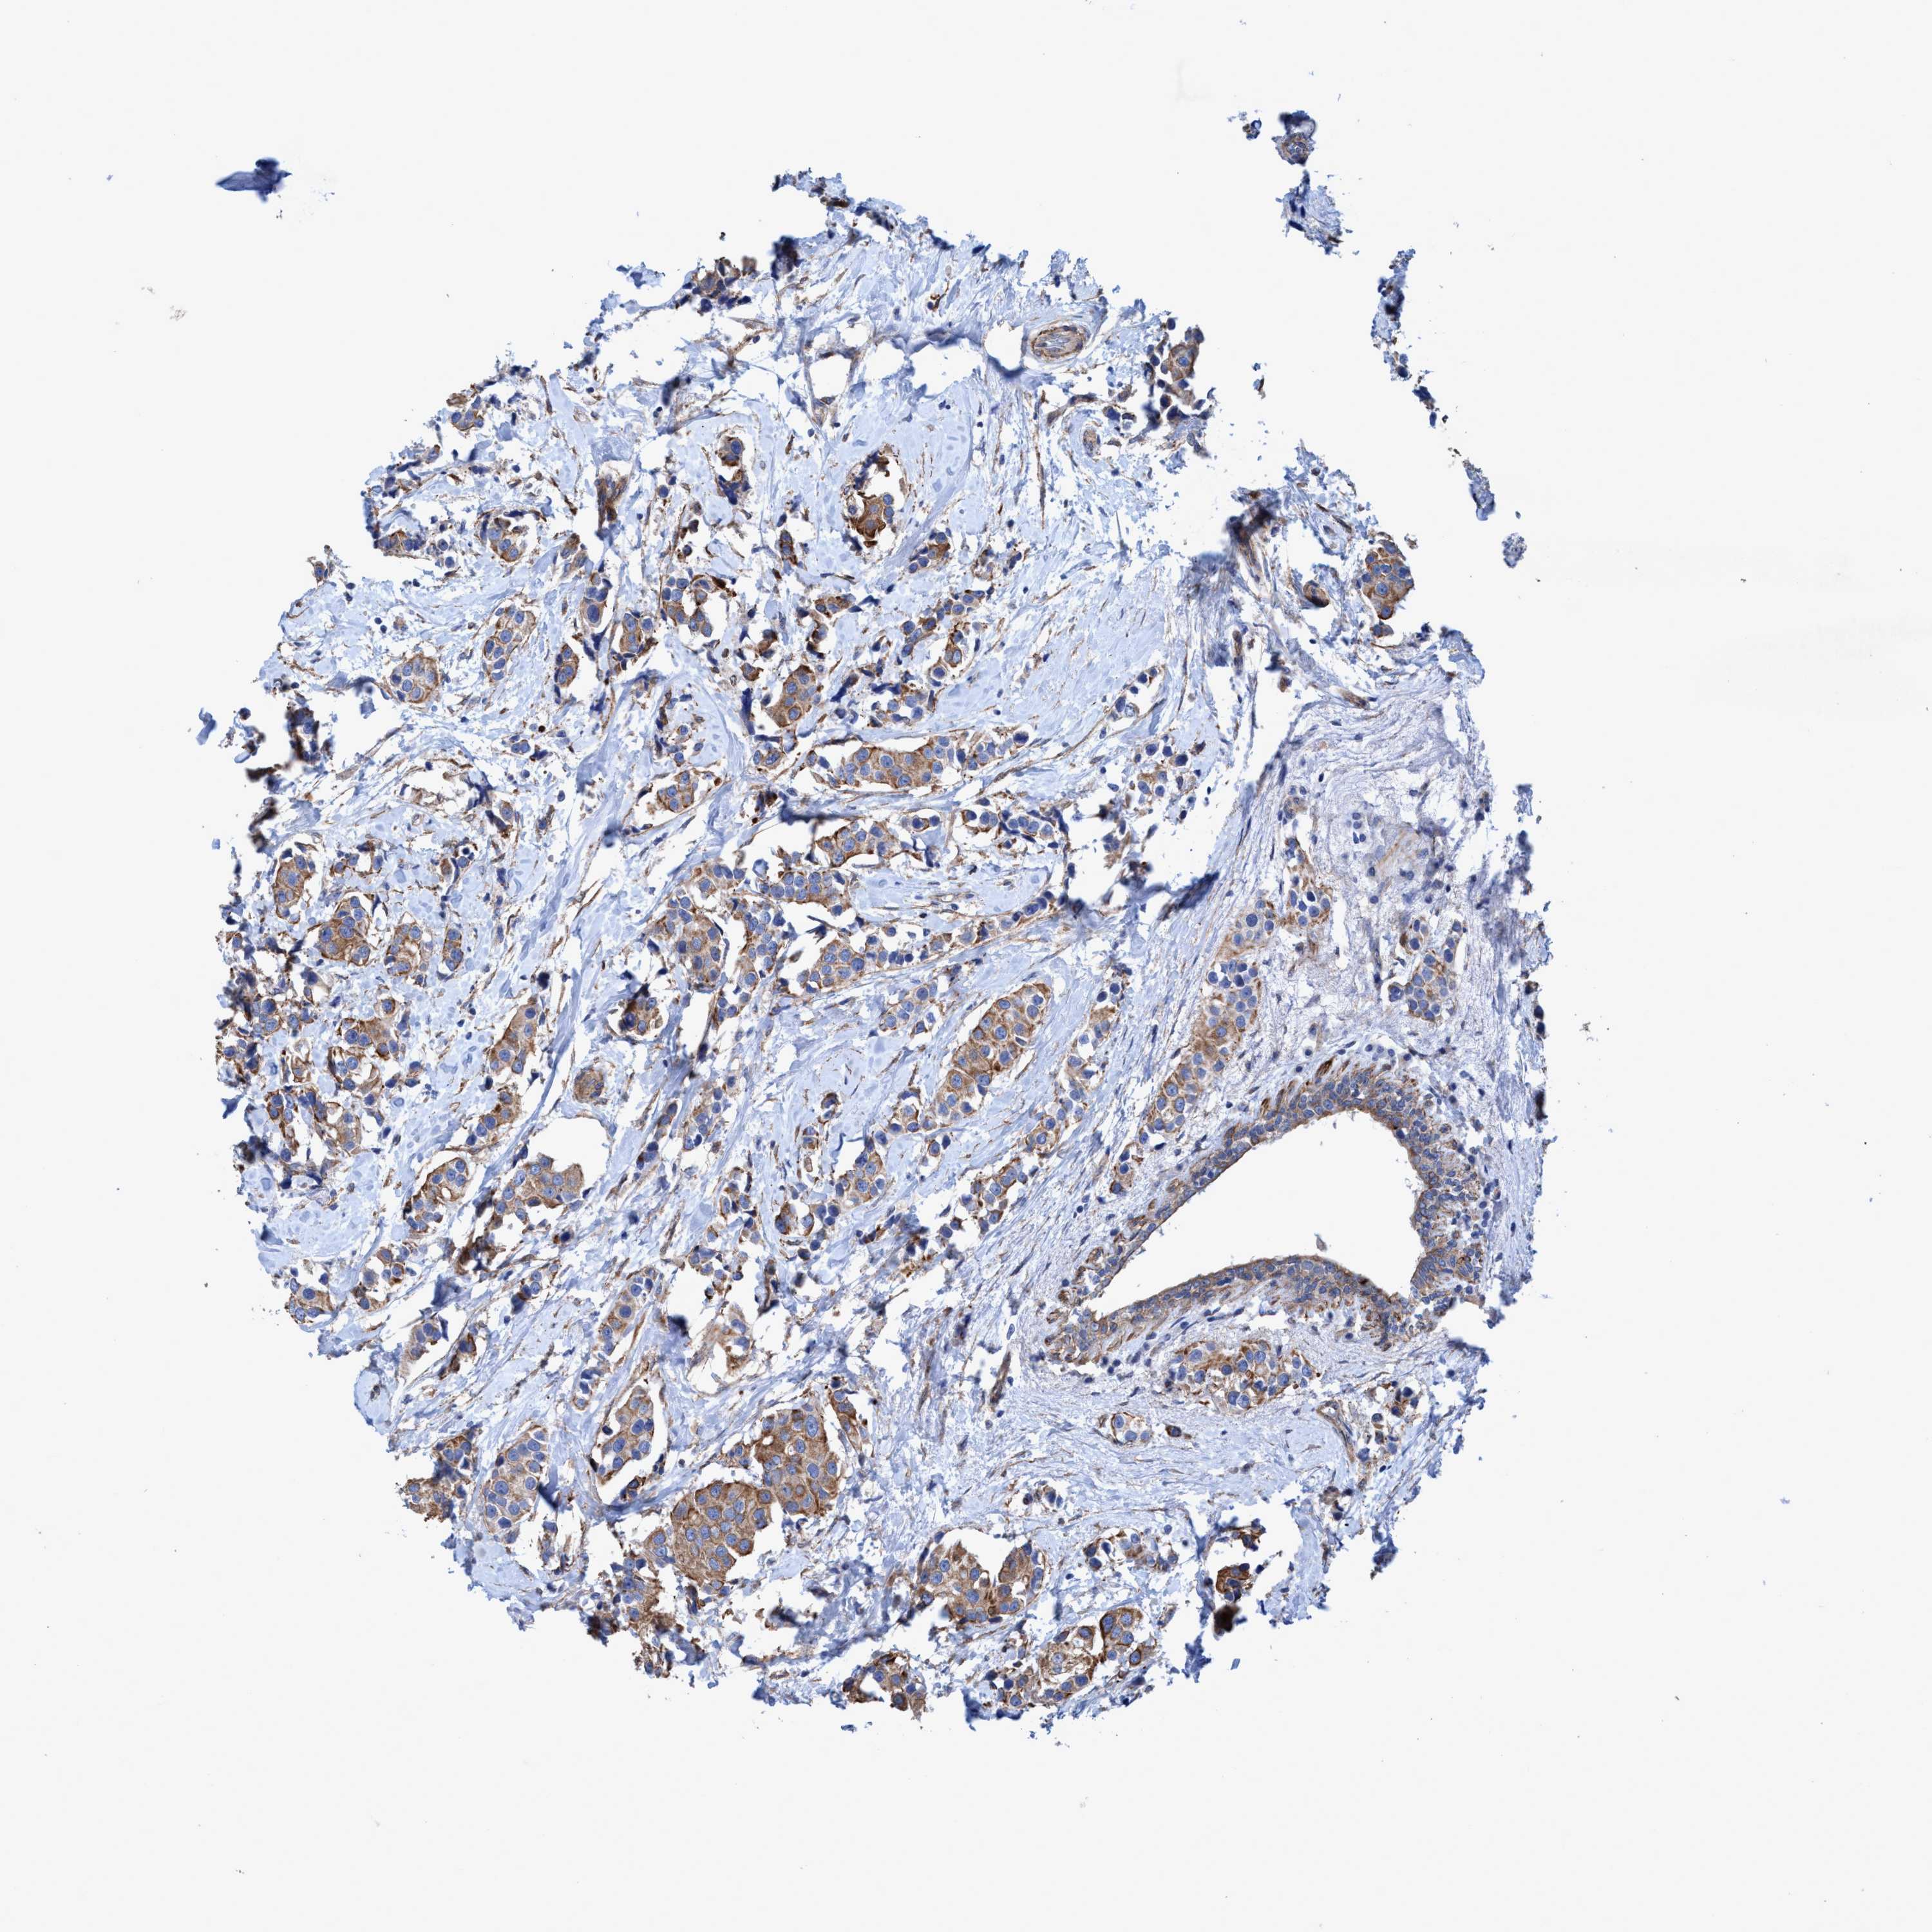

BRCA TCGA BRCA VALIDATION PROTEIN EXPRESSION

ANTIBODIES

AND

VALIDATION